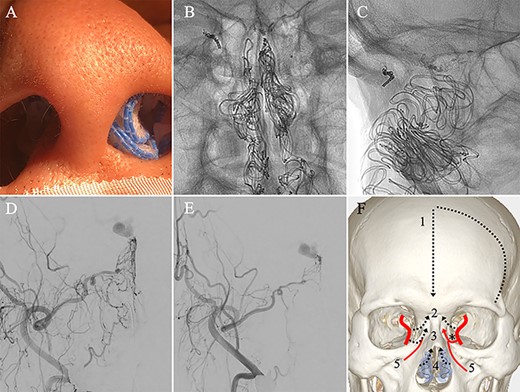

A patient in their 70s with extracranial lymphoma was incidentally found to have ACF–dAVF via head computed tomography and magnetic resonance angiography. Digital subtraction angiography (DSA) confirmed ACF–dAVF with multiple feeding branches, arising from bilateral OphAs, distal IMAs and the left middle meningeal artery (MMA), with cortical venous reflex (Borden type III, Cognard type IV) (Fig. 1). At the patient’s request, we chose endovascular, rather than surgical, treatment. We injected a 20% N-butyl-2-cyanoacrylate (NBCA)–lipiodol mixture into the fistula through bilateral ethmoidal arteries and the left MMA after we placed coils at the terminal branch of the right OphA. However, we could not achieve full penetration into the fistulous connections because of pressure secondary to high flow from the IMA branches, which resulted in incomplete obliteration (Fig. 1). Four months later, we repeated TAE by temporarily reducing nasal blood flow by inserting gauze infiltrated with xylocaine and epinephrine into the nasal cavities. After introducing the guiding catheter, an endonasal surgeon inserted X-ray-detectable surgical gauze infiltrated with 1% xylocaine and epinephrine (1:10 000) into bilateral nasal cavities using a nasal speculum, while paying full attention to avoid damage to the nasal mucosa. Then, we confirmed that the gauzes were placed in appropriate locations in the upper nasal cavity under fluoroscopic guidance. Immediately after insertion, we were able to confirm decreased blood flow from the IMA using DSA (Fig. 2). After this procedure, we navigated a DeFrictor Nano Catheter (Medico’s Hirata, Osaka, Japan) into the terminal branch of the OphA, which was connected to the dorsal nasal artery. Even though there was still a distance from the tip of the microcatheter to the shunt pouch, the NBCA reached the shunt point and penetrated the venous portion (Fig. 3). Follow-up DSA demonstrated complete obliteration of the ACF–dAVF, and blood flow in the nasal mucosa from the IMA branches recovered normally (Fig. 4).

Right (A) and left (B and C) internal carotid artery angiography before initial treatment showing ACF–dAVF with feeding arteries arising from branches of the OphAs; ethmoid artery (arrow) and dorsal nasal artery (arrowhead) (D and E). Bilateral external carotid artery angiography before initial treatment, anteroposterior view, showing the ACF–dAVF fed by bilateral distal internal maxillary arteries and the left middle meningeal artery.